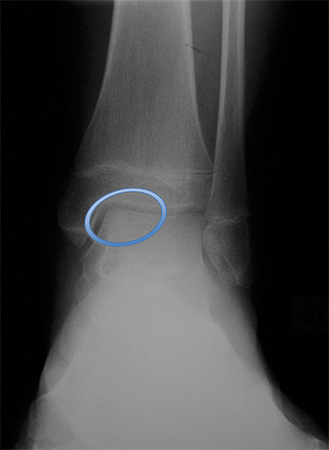

Stimulating the development of hyaline cartilage (autologous chondrocyte implantation, osteochondral allograft or autograft).[42] Each of these techniques has advantages and disadvantages. Studies have yet to show which salvage technique provides the best outcome.[Figure caption and citation for the preceding image starts]: Osteochondral lesion of medial talusFrom the collection of H. Chambers, MD [Citation ends].